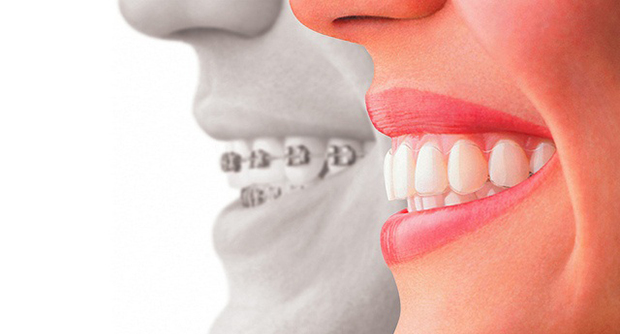

Types of Dental Crowns

Dental crowns can be fabricated from several materials. The choice depends on your preferences and the condition of the tooth.

- Porcelain fused to Metal Crowns:

- They are fabricated from a base metallic layer covered by a porcelain layer that matches your tooth colour.

- They can be used on both front and back teeth or when there is a greater need for strengthening teeth and improving aesthetics.

- They may cause wear on the natural dentition, the porcelain layer may chip or break, and the metal layer may exhibit a thin dark line at the margins.

- All-porcelain (ceramic) crowns:

- Dental crowns are fabricated from porcelain or ceramic material exclusively.

- The ceramic crown may be milled as one piece from a ceramic block that matches your tooth colour using a CAD/CAM machine or by pressing an inner ceramic core to form a framework similar to metal, then porcelain layers are added.

- They provide superior aesthetics and a natural-looking appearance compared to all other types of crowns, as they mimic the natural translucency of a tooth.

- It can be used on the front and back teeth.